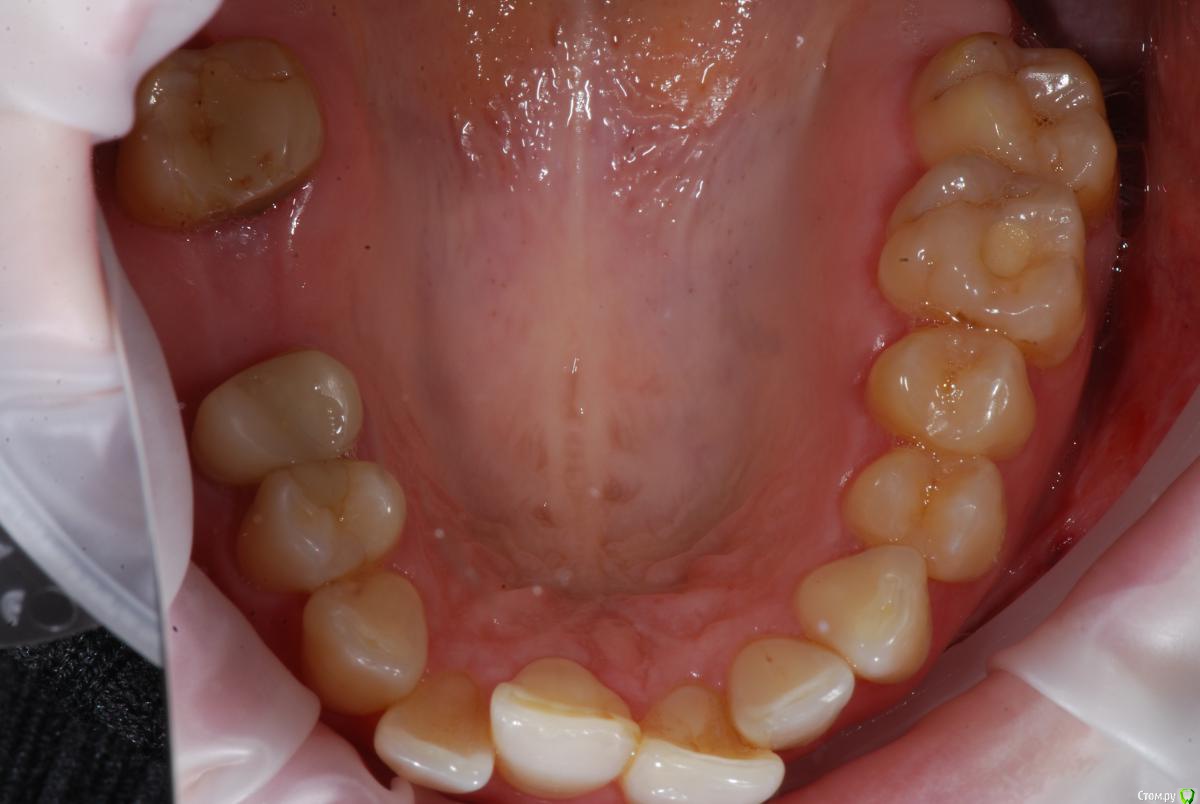

Afffinity Опубликовано 13 декабря, 2016 Автор Поделиться Опубликовано 13 декабря, 2016 Вот именно в чем в принципе сомневаетесь? и на моделях надо указывать анатомический центр, тогда сразу понятнее станет чего и куда и на сколько. ну Вы хотя бы свои мысли озвучили бы, расчет трг, характер асимметрии (в каком положении головки, что на КТ?) ... полностью Вам не распишут план, вопросы более конкретные попробуйте задать для коллегЕсли кратко то по расчетам ТРГ 2й скелетный класс, в цифрах завтра распишу. Прошу прощения что сразу не выложил. 2е, смущает смещение центральной линииПланируем установить систему Damon Q. Самый главный вопрос, возмножо ли в данном случае обойтись без удаления премоляров? Ссылка на комментарий